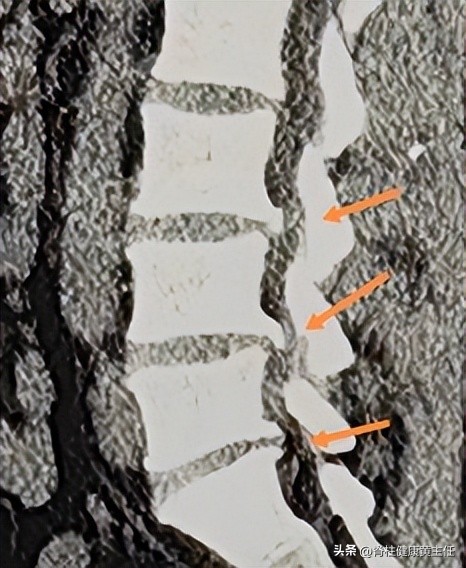

2023.2.22外院腰椎MR报告:L3/4、L4/5、L5/S1椎间盘膨出并突出,L3/4、L4/5水平椎管狭窄,L4/5、L5/S1双侧侧隐窝狭窄并神经根受压。

2023.03.18外院腰椎CT报告:L3/4、L4/5、L5/S1椎间盘向后突出,相应硬膜囊受压,L4/5、L5/S1双侧神经根受压。